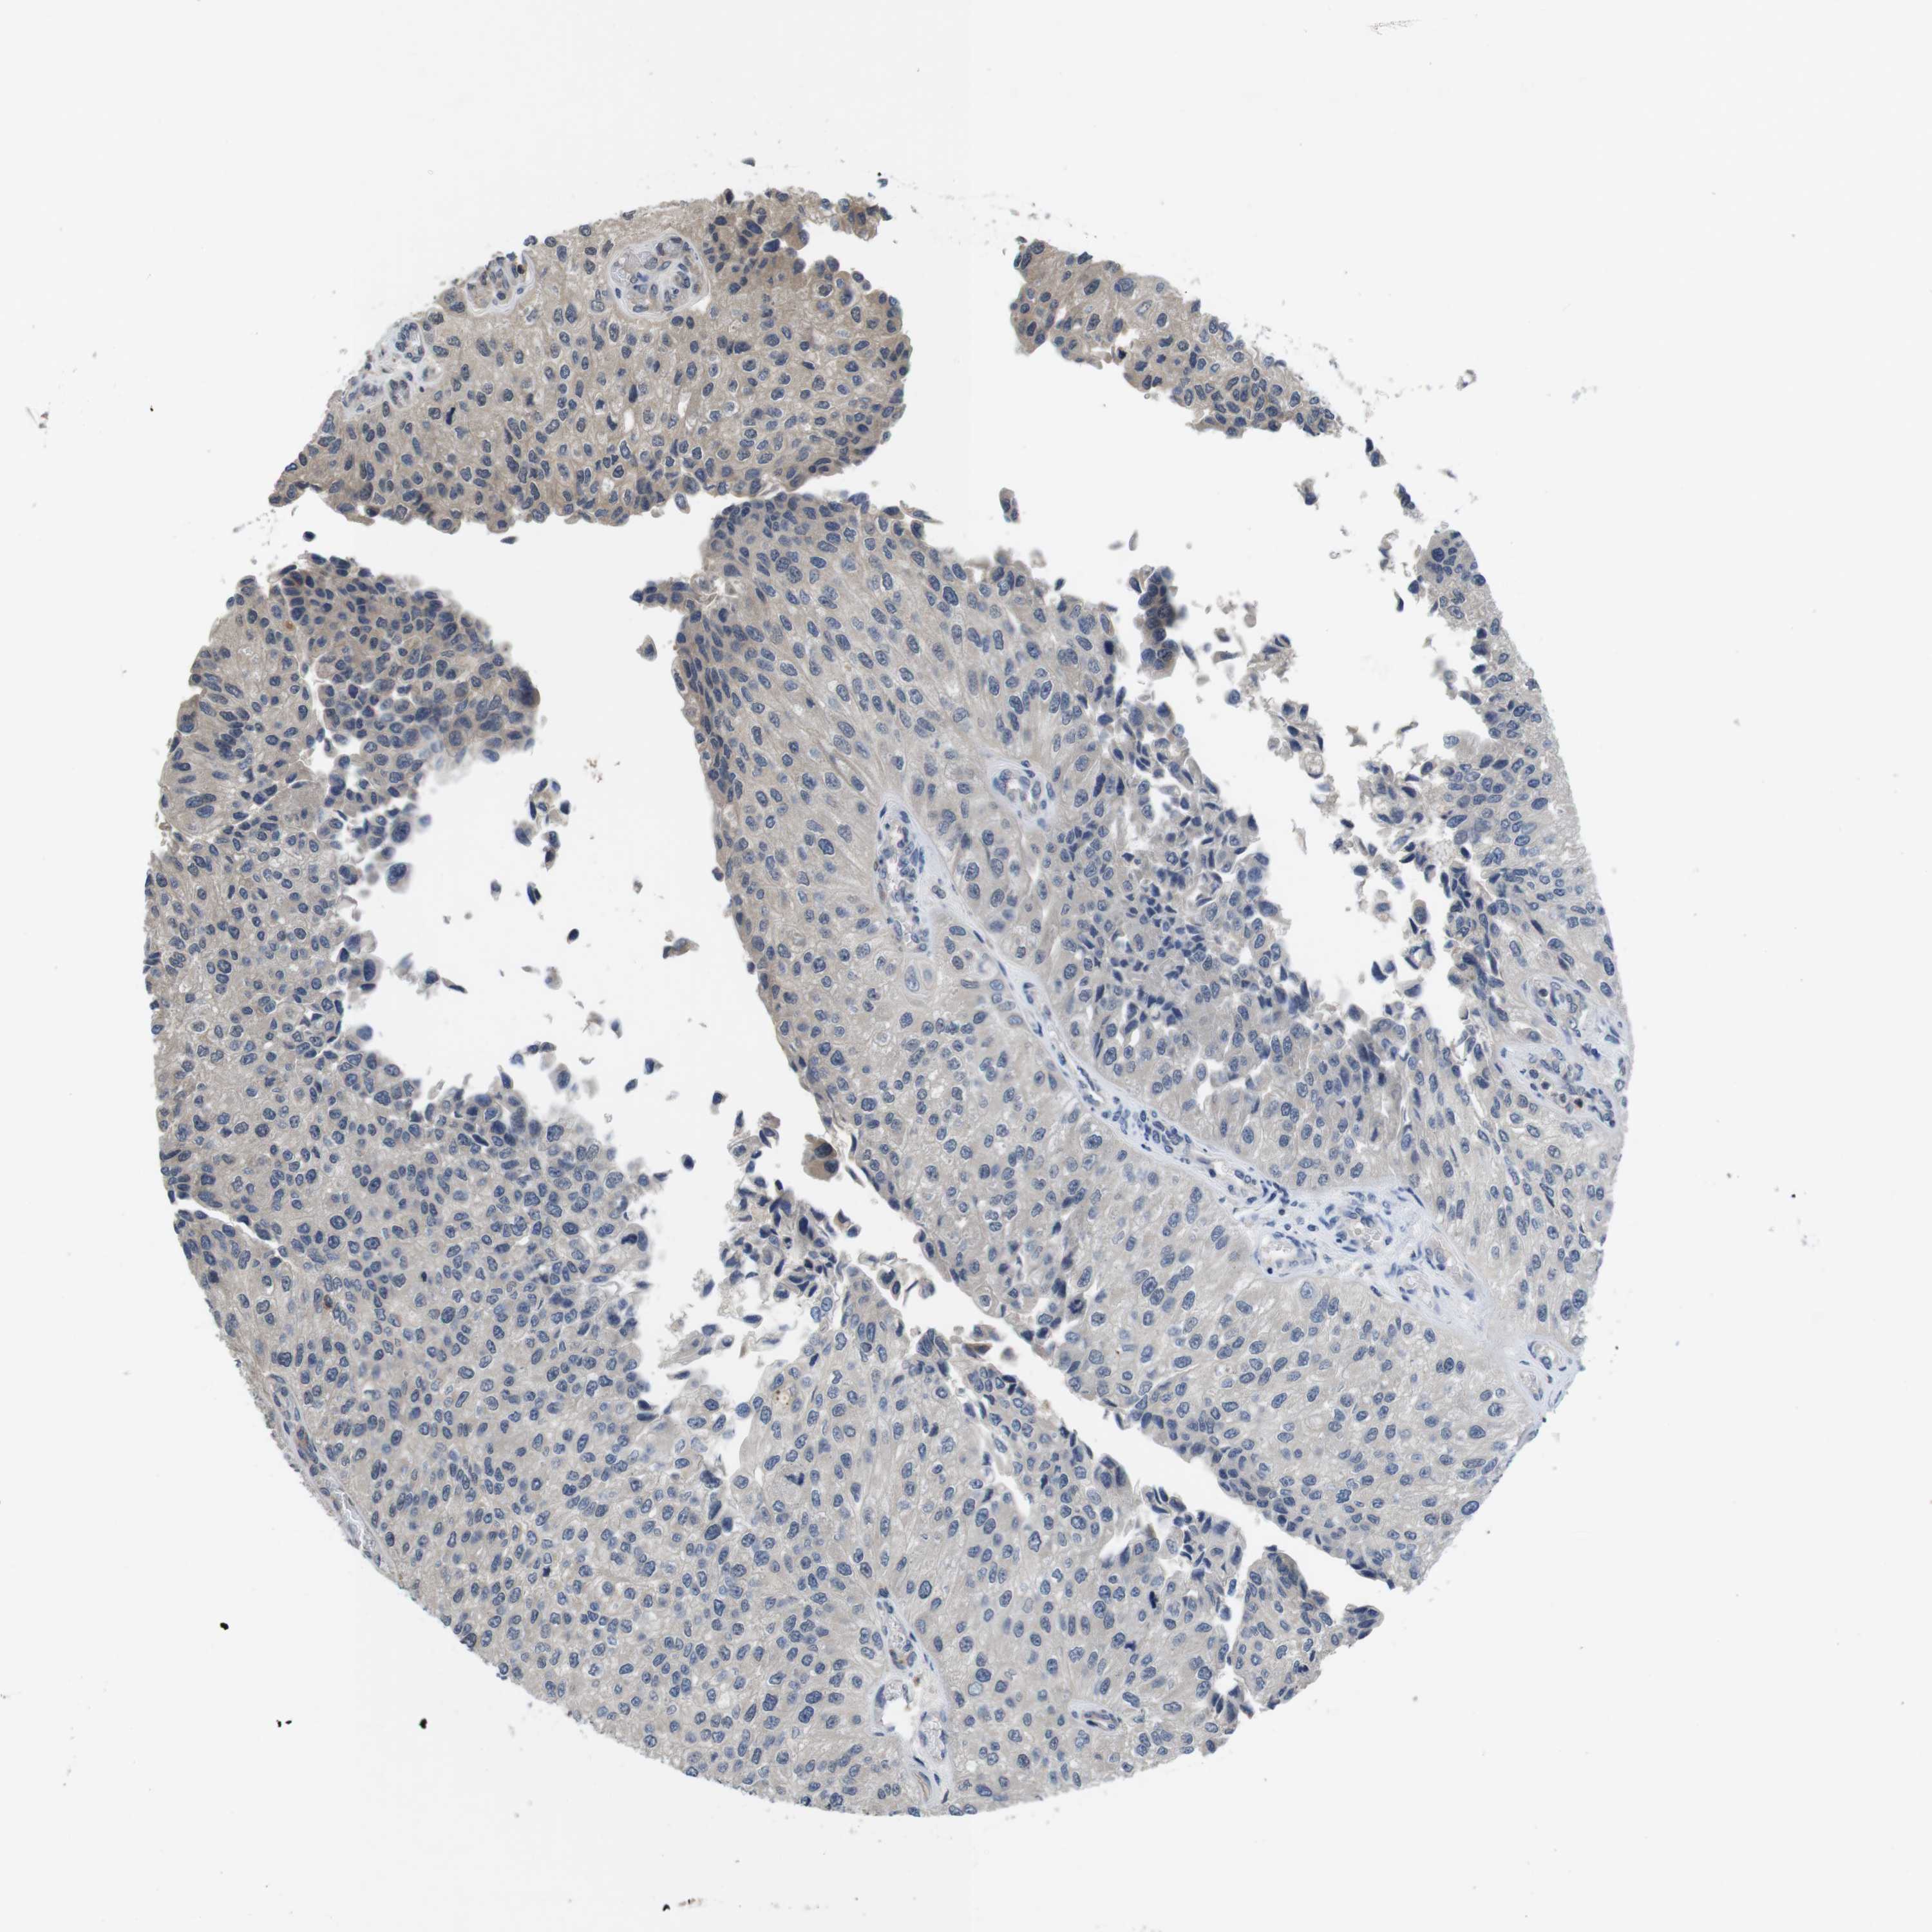

UROTHELIAL CANCER - Protein expressioni

A mouse-over function shows sample information and annotation data. Click on an image to view it in a full screen mode. Samples can be filtered based on level of antibody staining by selecting one or several of the following categories: high, medium, low and not detected. The assay and annotation is described here.

Note that samples used for immunohistochemistry by the Human Protein Atlas do not correspond to samples in the TCGA dataset.

Antibody stainingi

Antibody staining in the annotated cell types in the current human tissue is reported as not detected, low, medium, or high, based on conventional immunohistochemistry profiling in selected tissues. This score is based on the combination of the staining intensity and fraction of stained cells.

Each image is clickable and will lead to virtual microscopy that enables deeper exploration of all samples and also displays staining intensity scores, fraction scores and subcellular localization as well as patient and tissue information for each sample.

Antibody HPA001464

Antibody CAB010209

Urothelial carcinoma, Low grade